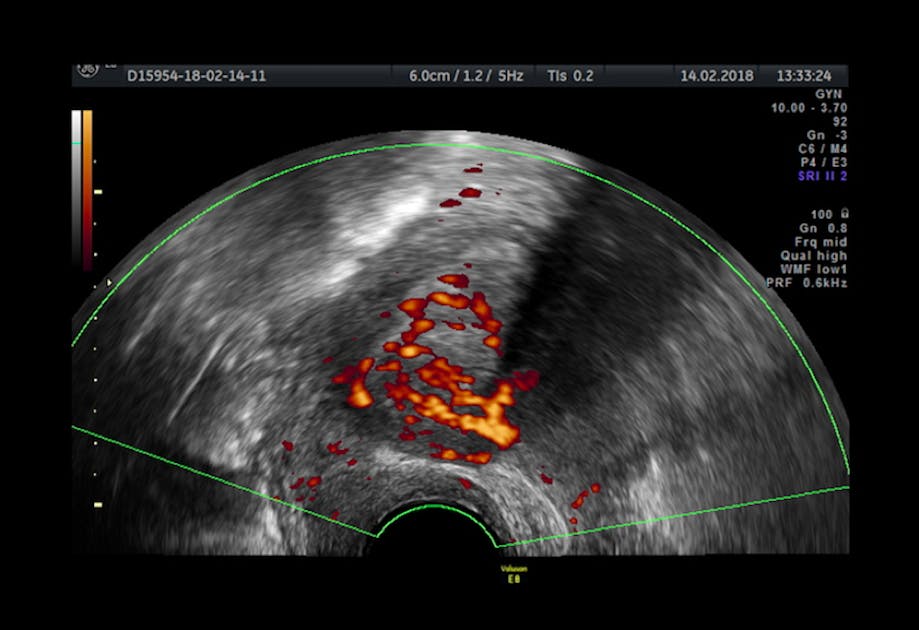

Cancer of the endometrium or the ovaries is one of the most severe conditions that can lead to an increase in endometrial thickness. Symptoms of uterine cancer that are different from uterine fibroids include abnormal vaginal bleeding (bleeding that is not part of a menstrual period, bleeding after menopause), or a mass in the vagina. According to the american cancer society, endometrial cancer is. Women with hypertension and diabetes (particularly type 2) have an increased risk for endometrial cancer, which may reflect the presence of common risk factors such as obesity., If you have symptoms or believe you may be at high risk for uterine cancer, your doctor may perform an endometrial biopsy or a transvaginal ultrasound. When your endometrium thickens, it can lead to unusual bleeding. Specifically, you'll want to look for these common symptoms of endometrial cancer: I just wrote a long text about my specific type of uterine/endometrial cancer. Exams are generally completed in conjunction with your pap test, a procedure to collect cells from the surface of the cervix and vagina. Every person eventually finds a way to cope with an endometrial cancer diagnosis. People who have abnormal vaginal bleeding before the test may still need a dilation and curettage (d&c; Would you please write down the kind of cancer you think i might have? If you start spotting, even very slightly, call your doctor.

In 2021, about 66,570 new uterine cancer cases are expected to be diagnosed in the united states, according to the american cancer society. Most appointments to diagnose endometrial cancer begin with a pelvic exam to check for abnormal areas or lumps around your vagina, cervix, uterus, fallopian tubes, ovaries, and rectum. If you have symptoms or believe you may be at high risk for uterine cancer, your doctor may perform an endometrial biopsy or a transvaginal ultrasound. Symptoms of uterine cancer that are different from uterine fibroids include abnormal vaginal bleeding (bleeding that is not part of a menstrual period, bleeding after menopause), or a mass in the vagina. I just wrote a long text about my specific type of uterine/endometrial cancer. Your doctor may do this test in his or her office, or may refer you to another doctor. Signs that warrant an immediate trip to a doctor some common cancer signs that should result in a visit to the emergency room or to a doctor as soon as possible include: If you are concerned about any changes you experience, please talk with your doctor. Over 80 percent of mcts develop during reproductive years. The international federation of gynecology and obstetrics classifies endometrial cancer into four stages: Find out enough about endometrial cancer to make decisions about your care. The most likely symptoms are: How does the doctor know i have endometrial cancer?€€ endometrial cancer may be found after a woman goes to a doctor because she has

Symptoms of uterine cancer that are different from uterine fibroids include abnormal vaginal bleeding (bleeding that is not part of a menstrual period, bleeding after menopause), or a mass in the vagina. I understand that it has spread, but surely something must. Over 80 percent of mcts develop during reproductive years. If you're worried about endometrial cancer, you need to pay attention to your body. If you have symptoms or believe you may be at high risk for uterine cancer, your doctor may perform an endometrial biopsy or a transvaginal ultrasound. I'm trying to not dwell on it or the upcoming cat scan come dec7th but you have to admit it's stressful and it sucks! In this test, the doctor takes out a small piece of the endometrium to check it for cancer cells. See below), even if no abnormal cells are found during the biopsy. How does the doctor know i have endometrial cancer?€€ endometrial cancer may be found after a woman goes to a doctor because she has People who have abnormal vaginal bleeding before the test may still need a dilation and curettage (d&c; Would you please write down the kind of cancer you think i might have? With metastatic endometrial cancer the growth has spread beyond the uterus, first entering the blood stream, traveling to the lymph nodes, and eventually spreading. In 2021, about 66,570 new uterine cancer cases are expected to be diagnosed in the united states, according to the american cancer society.